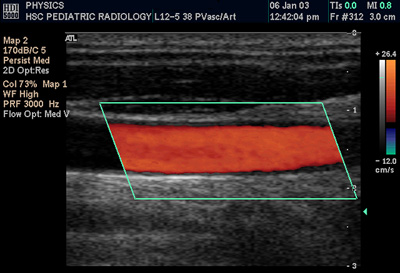

도플러 효과는 반사된 음파의 주파수 변화를 이용하여 대상 물체가 초음파 탐촉자(프로브)에 가까워지는지 또는 멀어지는지를 판단하고 이를 영상으로 나타내는 기술이다.[58][61] 특정 위치에서 초음파 빔의 주파수 변화를 측정하여 혈류와 같은 구조물의 속도와 방향을 평가할 수 있다.

- 컬러 도플러: B 모드 영상 위에 특정 영역 내 혈류의 평균 속도와 방향을 색상으로 표시한다. 일반적으로 탐촉자로 다가오는 혈류는 붉은색 계열로, 멀어지는 혈류는 푸른색 계열로 나타낸다. 이는 물리학에서 적색편이가 멀어짐을, 청색편이가 가까워짐을 나타내는 것과는 반대이다. 컬러 도플러는 혈류의 전반적인 분포와 방향을 직관적으로 파악하는 데 유용하다.

- 이중 초음파 (Duplex ultrasonography): 회색조의 B-모드 영상과 컬러 도플러 또는 스펙트럼 도플러 영상을 동시에 표시하는 방식이다. 이를 통해 해부학적 구조와 혈류 정보를 함께 평가할 수 있다.[62]

몸 표면에서 기기를 이용하여 복강 내의 대동맥, 대정맥이나 팔다리의 동맥, 정맥 상태를 평가한다. 특히 경동맥이나 다리의 동맥 및 정맥에 발생할 수 있는 협착(좁아짐), 폐쇄(막힘), 혈전(피떡) 등을 진단하는 데 유용하게 사용된다.6. 7. 응급의학과